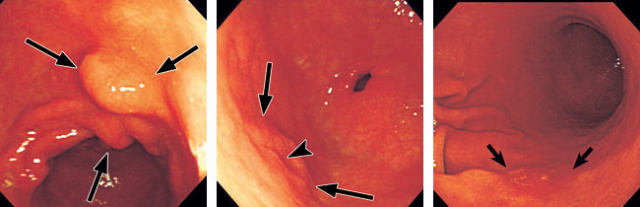

- 위암 초기증상 : 위축성 위염

위축성 위염이 있으면 위암에 걸릴 확률이 6배 더 높다고 합니다. 또는 이미 위축성 위염이 발생했다면 위가 다시 정상적으로서 회복되지 않을 수 있어요. 따라서 일정 기간 동안 내시경 검사를 통해 후속 조치를 취하는 것이 필요합니다. 짠 식품을 피하는 것도 매우 필요합니다. 위축성 위염은 위산 분비가 눈에 띄게 떨어뜨리여 소화 행동이 저하돼요. 또는 위암으로써 이어지는 것은 위 점막 세포의 변형이라고 해요.